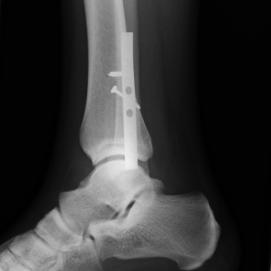

Röntgenbilder